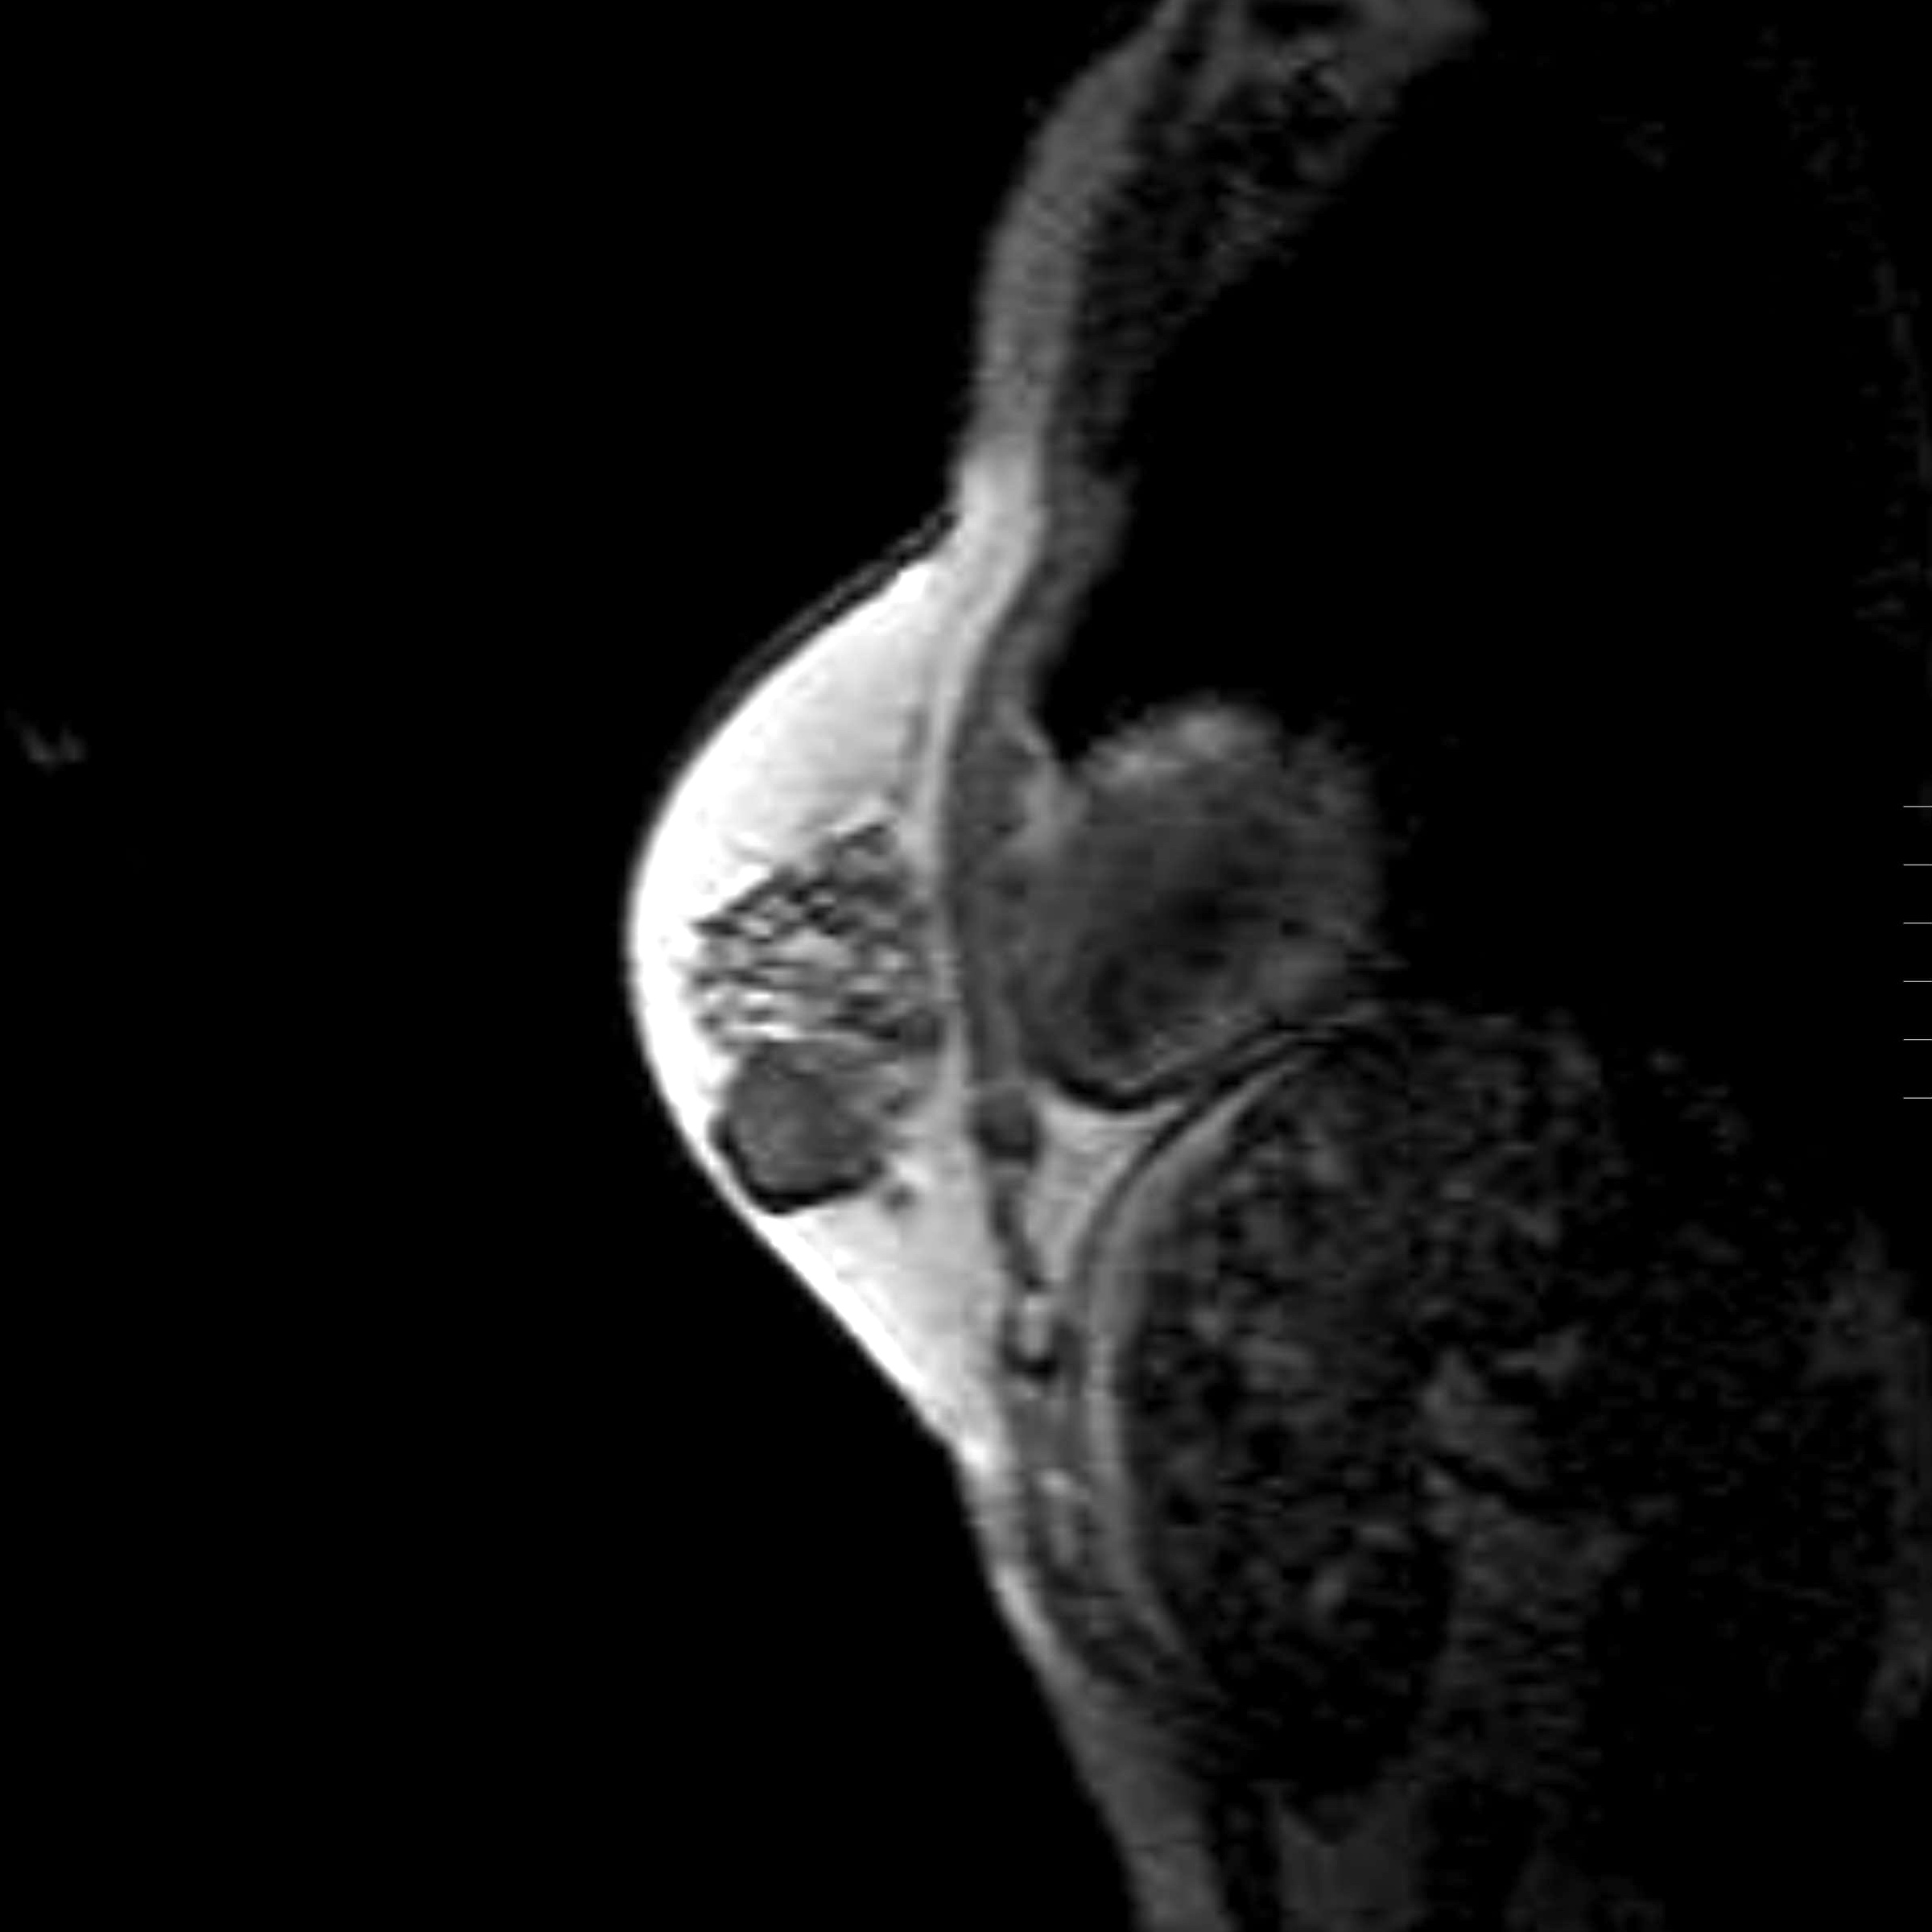

Radiology description

- Conventional imaging modalities for assessment of radiological response includes mammography, ultrasound, MRI

- Radiological response is defined by resolution of original imaging finding (complete response) or by change in lesion size

- Radiological response is predictive of outcome and correlates with pathological response (Eur J Surg Oncol 2021;47:232)

- MRI is more sensitive and is preferred over other imaging modalities (Anticancer Res 2014;34:1219, Insights Imaging 2013;4:163)

- Functional imaging is also used for assessment of radiological response

- Response is defined by normalization of tracer uptake (complete response) or by change in tracer uptake (Radiology 2017;285:358)

- MRI is more accurate in predicting complete pathological response than PET / CT (Oncologist 2016;21:931)

Radiology images